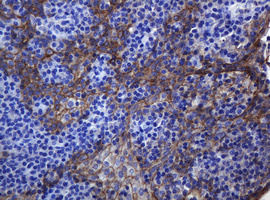

Immunohistochemical staining of paraffin-embedded Human tonsil within the normal limits using anti-CDH1 mouse monoclonal antibody. (Heat-induced epitope retrieval by 10mM citric buffer, pH6.0, 120°C for 3min, M00063-5)